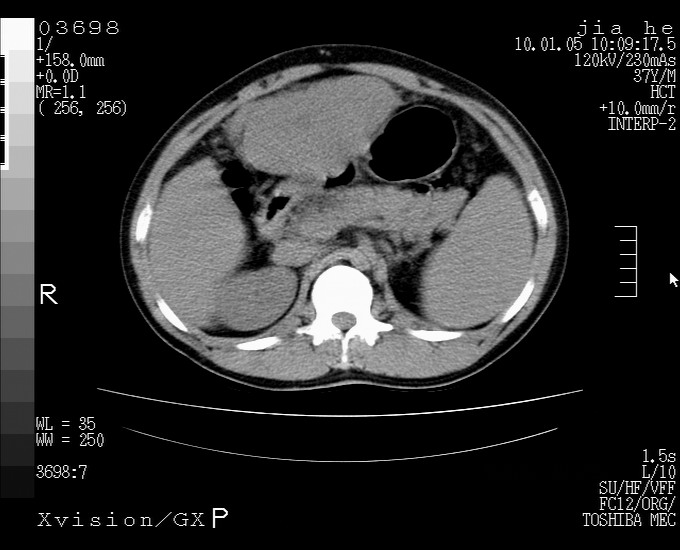

标题: CT23988:男,40岁,B超提示腹部肿物,请各位老师给看看。 [打印本页]

标题: CT23988:男,40岁,B超提示腹部肿物,请各位老师给看看。

左叶够大的,且与胰腺欠清晰,请增强扫描

考虑肝癌 请强化

肝癌并腹膜后淋巴西结转移

1.该患者有腹部手术史

2.脾大,肠系膜密度增高,有多发索条影,胰腺边缘毛糙,腹膜增厚,推测有肝硬化,门脉高压,腹膜炎和/或胰腺炎

3.肝左叶巨大站位,并腹腔淋巴结肿大,肝癌或肝间叶来源恶性肿瘤,也不排除大网膜间质瘤侵及肝左叶

建议:增强或磁共振

肝癌并腹膜后淋巴结转移

外生性肝癌并腹膜后淋巴西结转移!

考虑肝左叶外侧段癌并腹膜后淋巴结转移.建议增强进一步检查.